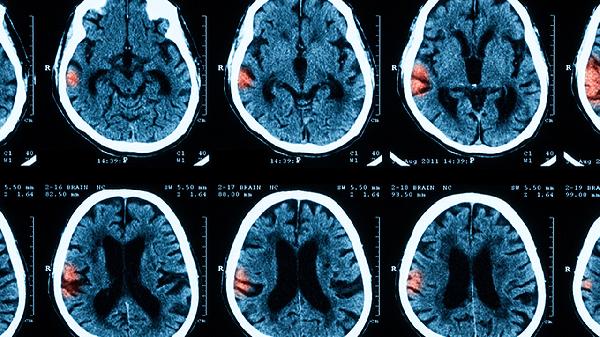

孩子得了脑膜炎有哪些表现

儿童脑膜炎的常见症状包括发烧、头痛、呕吐、颈部僵硬以及精神状态的变化。病情的发展通常分为几个阶段:初期可能有发热和食欲下降,进入进展期后会出现剧烈头痛和喷射性呕吐,到了晚期则可能出现意识障碍和抽搐。